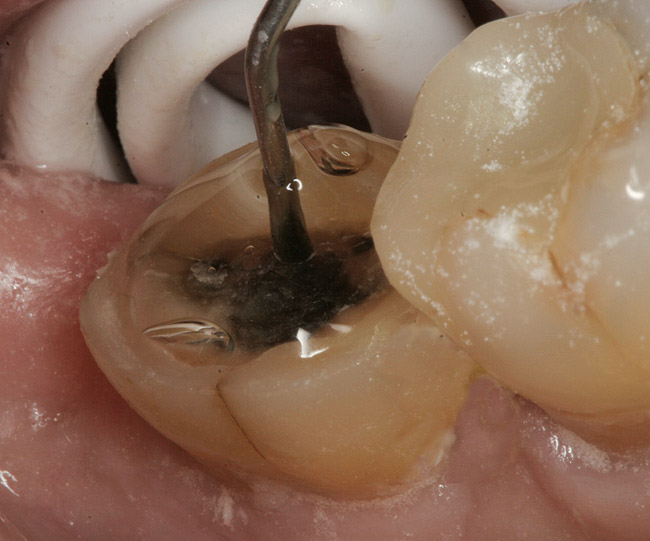

A 70-year-old patient presented with symptoms of a cracked tooth scenario, with intermittent pain upon chewing and thermal sensitivity. The diagnosis was supported through various tests, which determined the lower right second molar had an incomplete fracture that extended from the distal marginal ridge to the mesial marginal ridge. After treatment options were presented, an all-ceramic restoration was decided upon. The tooth was prepared for a nonretentive, adhesively retained all-ceramic restoration ("table top" preparation) (Figure 2 and Figure 3). After the preparation was completed a mild self-etching adhesive was applied to the dentin according to the manufacturer's instruction (Figure 4). There was little concern, if any, of the adhesive reaching the band of exposed enamel. The adhesive was light-polymerized for 5 seconds to secure the layer to the dentin (Figure 5). To eliminate the oxygen-inhibited layer a water-soluble gel was applied to the adhesive and further light-polymerization was completed (Figure 6 and Figure 7). For direct digital scanning cases in which a powdering technique is employed for image capture, it may be more difficult to remove the powder after scanning if the oxygen-inhibited layer is still present.

Figure 4  Application of a self-etching adhesive immediately after completion of tooth preparation.

Figure 4